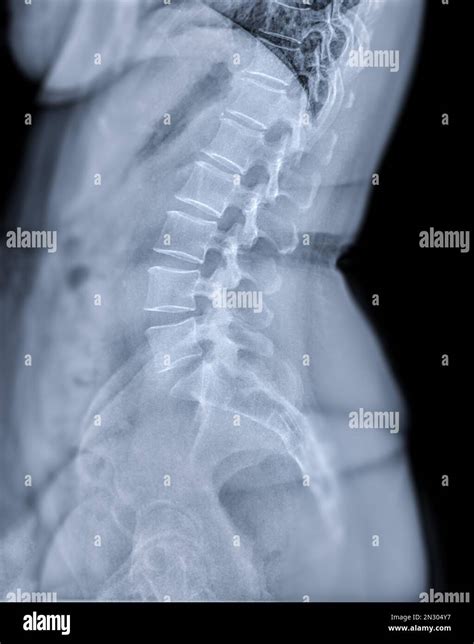

Dealing with persistent discomfort in your spine can be an overwhelming experience, leading many people to seek professional medical imaging. A back X-ray is often the first diagnostic step physicians recommend when assessing structural issues, injuries, or chronic pain in the vertebral column. By using a small dose of ionizing radiation, this imaging technique produces detailed pictures of the bones, allowing doctors to visualize the alignment, density, and integrity of your spine. Whether you are dealing with a sports injury, potential scoliosis, or long-term degenerative conditions, understanding what to expect during this procedure can significantly reduce anxiety and help you advocate for your own health.

Medical professionals utilize a back X-ray to evaluate a wide variety of symptoms. Unlike soft tissues, such as muscles, ligaments, or nerves, X-rays are specifically designed to capture clear images of hard, dense structures like bones. If you are experiencing unexplained pain, your doctor may order this test to rule out fractures, infections, or tumors that could be contributing to your discomfort.

Once the images are taken, a radiologist reviews the back X-ray for any abnormalities. They look for evidence of bone spurs, narrowing of the disc spaces, compression fractures, or irregular spinal curves. These findings are then compiled into a formal report, which is sent back to your primary healthcare provider or the specialist who ordered the test.

It is important to remember that a "normal" result on an X-ray does not necessarily mean you are not in pain. Because X-rays do not show soft tissue, they cannot always detect issues like herniated discs, muscle strains, or nerve impingements. In such cases, your doctor might follow up with an MRI or a CT scan to get a more comprehensive view of the surrounding tissues.